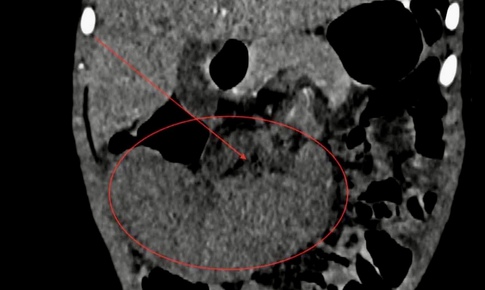

SKĐS - Lách xoắn ở trẻ em là một tình trạng cấp cứu y khoa hiếm gặp nhưng rất nghiêm trọng. Các bác sĩ Bệnh viện Hữu nghị Việt Nam – Cuba Đồng Hới vừa thực hiện phẫu thuật nội soi điều trị thành công cho bệnh nhi bị lách xoắn.